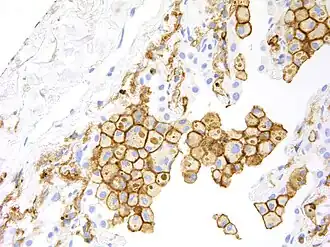

HAVCR2 expression is up regulated in tumor-infiltrating lymphocytes in lung,[8] gastric,[30] head and neck cancer,[31] schwannoma,[32] melanoma[33] and follicular B-cell non-Hodgkin lymphoma.[34] It is also up-regulated in tumour-associated macrophages in various malignancies, including melanoma, especially in immunotherapy-resistant context.[9]